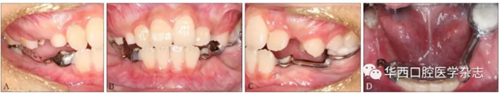

患者,男,10歲,2016年7月因右后牙未萌求治。無正畸治療史、拔牙史、全身系統疾病史,家族成員中無類似畸形。患者治療前口內像見圖1。

A:上頜面像;B:下頜面像;C:右側像;D:正面像;E:左側像。

圖  1   治療前口內像

臨床檢查:混合牙列,左側磨牙中性關系,前牙淺覆、淺覆蓋,右側側切牙反,下頜恒切牙及左下頜第一磨牙正常萌出,雙側下頜乳尖牙尚未脫落,下頜其余牙齒未見,黏膜色澤正常(圖1)。